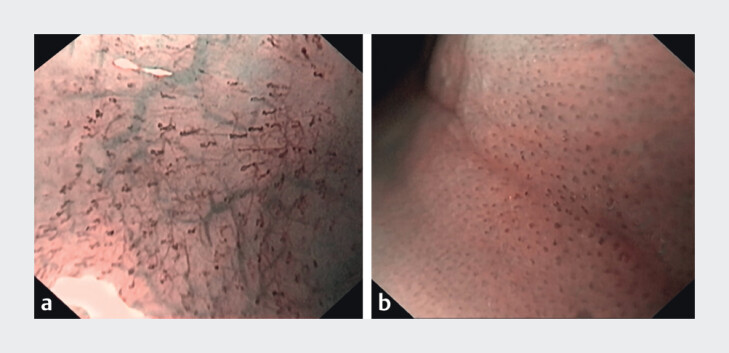

Background and study aims: Magnifying endoscopy with narrow-band imaging (ME-NBI) is regularly used in neoplasia diagnostics although its use in assessment of esophageal inflammatory changes is uncommon. The aim of this study was to evaluate the efficacy of eosinophilic esophagitis reference score and ME-NBI signs in predicting inflammation using gastroscopy with dual focus in patients with dysphagia.

Results: In total 219 patients (71.2% male) were enrolled to the study. Most frequent endoscopic findings were furrows (121/219, 55%), positive NBI signs (106/219, 48%), and edema (102/219, 47%). Logistic regression analysis showed that furrows and NBI signs were the most significant predictors of eosinophilic infiltration. Edema was the only significant predictor of lymphocyte infiltration.

Conclusions: Positive NBI signs and furrows were the best predictors of eosinophile infiltration, whereas lymphocytic infiltration was predicted by edema. Given that NBI is already widely available, we encourage use of both white light and NBI in patients with suspected esophageal inflammation.